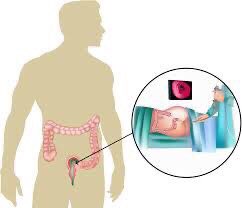

العلاقة بين #القولون_العصبي والمشاكل والأمراض النفسية علاقة مهمة ووطيدة

العلاقة بين #القولون_العصبي والمشاكل والأمراض النفسية علاقة مهمة ووطيدة

بالنهاية لازم نعرف أيش مُسببات القولون ومُهيجاته ونتجنبهم قد مانقدر ونعالج حدّة الأعراض ونخففها لأن مافيه علاج نهائي وتام .يارب إني وفقت في تقديم ما يحوز على رضاكم واذا أعجبكم الموضوع لا تنسوني ووالديني من صالح دعاكم وصحة وعافية للجميع يارب💙.